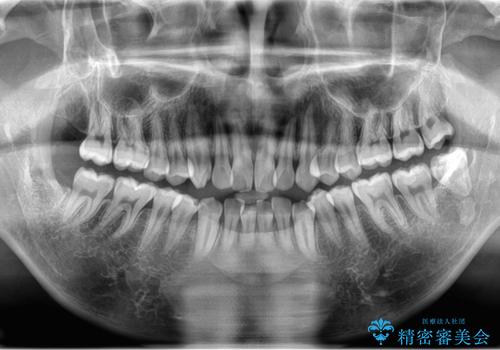

奥の虫歯 ジルコニアクラウンでの修復

左奥歯が痛い。(親知らず抜歯 ジルコニアクラウン)